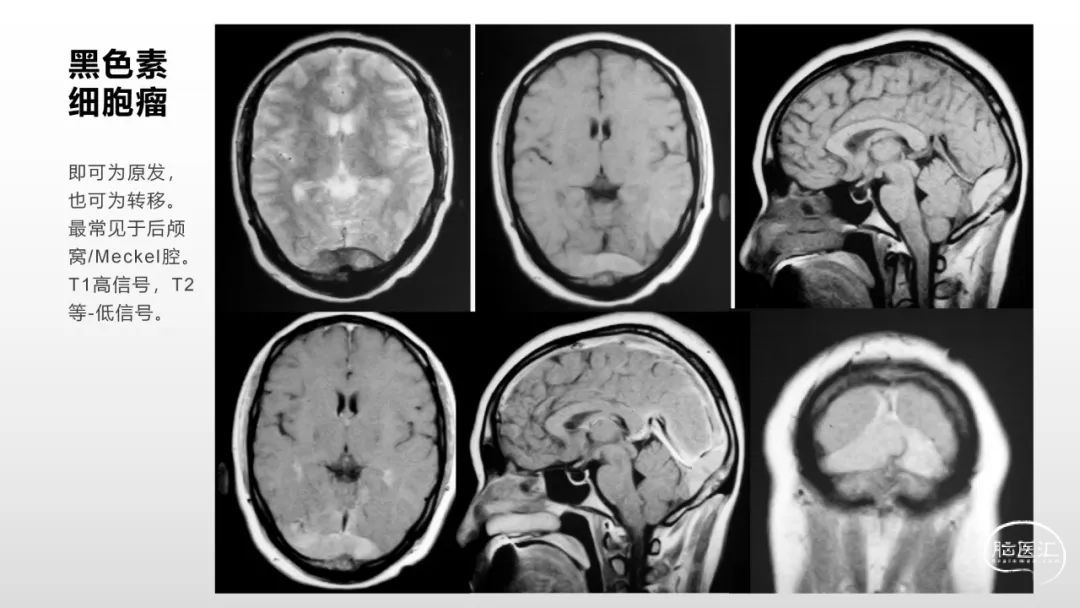

颅脑影像诊断基础知识讲座:脑膜病变